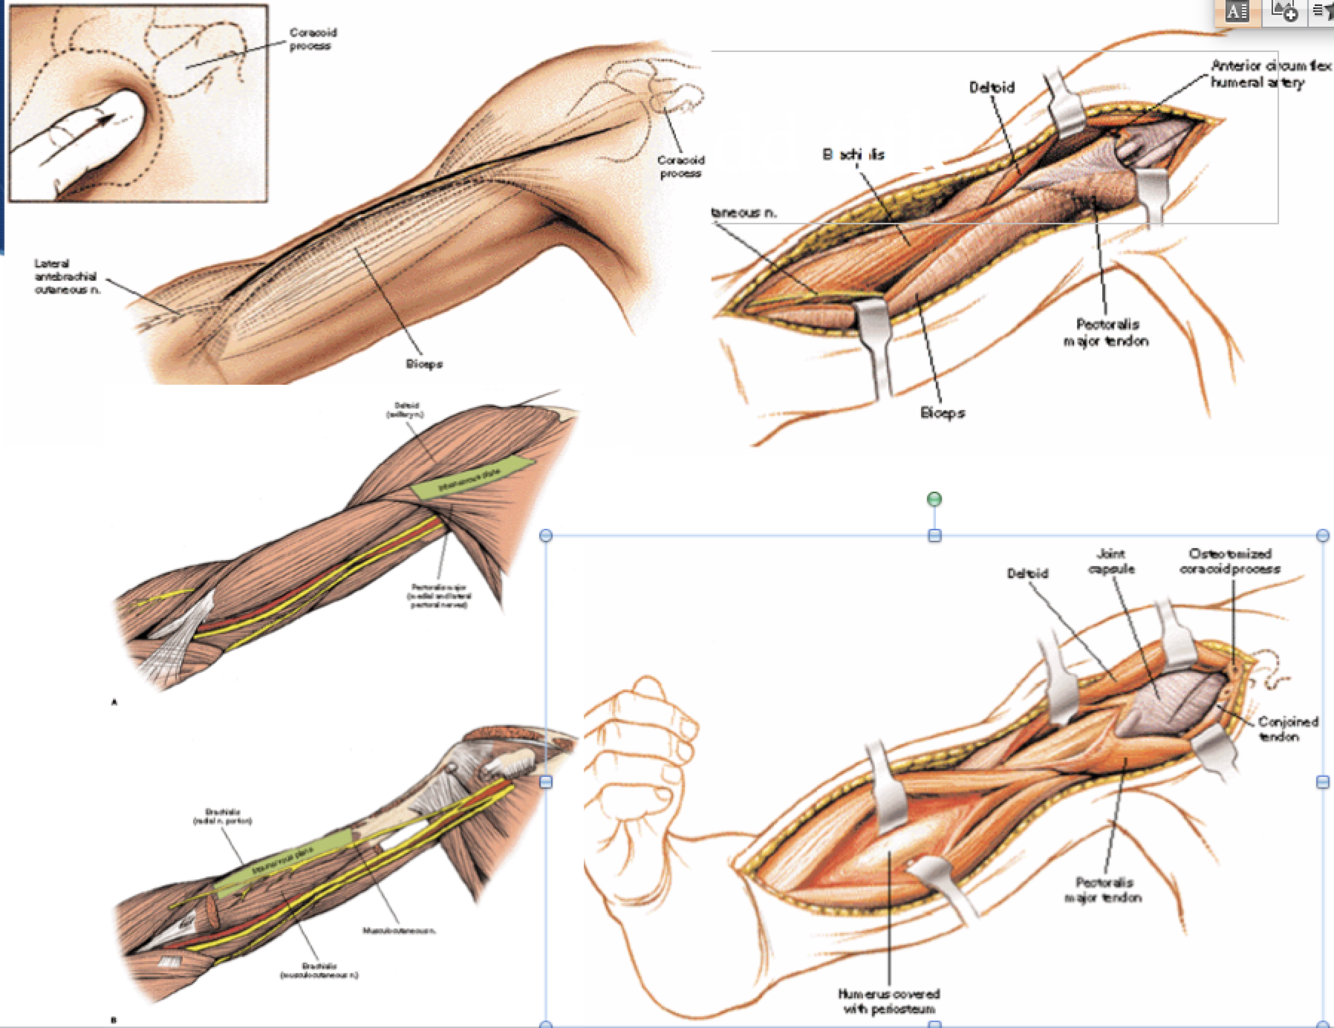

Anterolateral Approach Humerus

Interval:

- Proximal: Deltoid (Axillary N.) & Biceps (Musculocutaneous)

- Distal: Brachialis Split (Medial - Median n. lateral- radial N.)

Approach: Incision- coracoid to deltoid tuberosity then along lateral boarder of biceps. Establish deltopecotral interval, and separate between biceps and deltoid. As brachialis emerges, develelop split. Can be extended into a henry approach of the volar forearm.

Dangers: Musculocutaneous N. Deep to biceps, superficial to brachialis. Radial N. Between brachialis and brachioradialis laterally and in spiral groove. LABCN between brachialis and brachioradialis